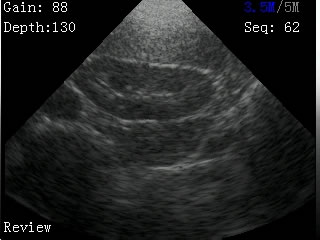

我司最新推出的V2型腕式B超,主机重量仅140克,看成目前全世界最轻的B超。

V2型腕式扇扫B超由主机、探头、外置电池、手握式键盘组成,重量只有140g(不含探头和电池)堪称全世界最轻的B超。

-扫描方式:机械扇扫

-探头频率:3.5MHz/5MHz双频率可变频探头

-扫描深度:≥180mm,70、110、130、150、192mm五档可调